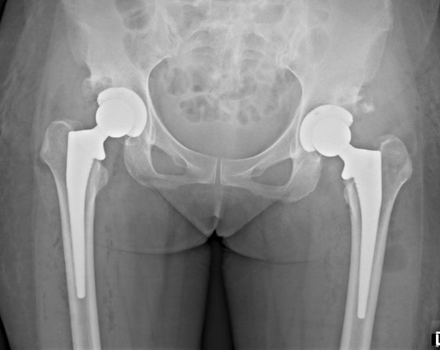

When is Total Hip Replacement Needed?

Total hip replacement (THR) becomes necessary when the joint damage is irreversible and conservative or regenerative treatments no longer provide relief. Key indicators for THR include:

- Severe Pain: Persistent pain that disrupts sleep, daily activities, or mobility despite other therapies.

- Bone-on-Bone Contact: Advanced cartilage loss (Stage 4 OA) confirmed by X-rays or MRI.

- Femoral Head Deformity: Structural damage to the femoral head (the "ball" of the hip joint), often due to avascular necrosis (bone death), severe OA, or congenital conditions like hip dysplasia. Deformity disrupts smooth joint movement, causing grinding, instability, and irreversible joint damage.

- Loss of Function: Inability to walk, climb stairs, or perform basic tasks due to stiffness or weakness.

- Joint Deformity: Visible changes in hip alignment or leg length discrepancy.

What is Total Hip Replacement?

THR involves surgically removing the damaged femoral head and acetabulum (hip socket) and replacing them with artificial components (prosthetics). Modern techniques and materials allow for durable, pain-free joint function in over 95% of cases.

BEFORE THR

AFTER THR